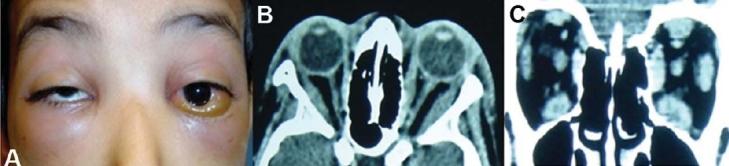

Orbital pseudotumor is a benign intraorbital process confined to the orbit but extra orbital involvement can occur. It is among the 3(rd) most common orbital diseases along with thyroid orbitopathy and lymphoproliferative disorder and accounts for 5-10% of orbital processes. Clinically, orbital pseudotumor has been categorized as myositis, dacryoadenitis, anterior, apical and diffuse process. Patients may present with diplopia, conjunctival chemosis, proptosis or abnormal computed tomography scan (CT-scan) findings. Patients may also have associated optic neuropathy. Diagnosis is based on careful history, ultrasonography (U/S), CT-scan and magnetic resonance imaging (MRI) studies which may also provide prognostic information. Treatment consists of systemic corticosteroids in the form of oral or intravenous administration. Confirmation is made by orbital biopsy. In addition to radiation, cytotoxic agents, immunosuppressant, IV immunoglobulin, biological therapy, TNF-alpha inhibitor monoclonal antibody and Mycophenolate Moftil have been found to be useful in the management of refractory orbital pseudotumor.

眼眶假瘤是一种局限于眼眶的良性眶内病变,但可发生眶外累及。它是与甲状腺相关眼病和淋巴增殖性疾病并列的第三常见眼眶疾病,占眼眶病变的5% - 10%。临床上,眼眶假瘤已被分类为肌炎型、泪腺炎型、前部型、尖部型和弥漫型。患者可能出现复视、结膜水肿、眼球突出或计算机断层扫描(CT扫描)异常表现。患者也可能伴有视神经病变。诊断基于详细的病史、超声检查(U/S)、CT扫描和磁共振成像(MRI)研究,这些检查也可能提供预后信息。治疗包括口服或静脉注射全身用糖皮质激素。通过眼眶活检进行确诊。除放射治疗外,细胞毒性药物、免疫抑制剂、静脉注射免疫球蛋白、生物疗法、肿瘤坏死因子-α抑制剂单克隆抗体和霉酚酸酯已被发现对难治性眼眶假瘤的治疗有用。